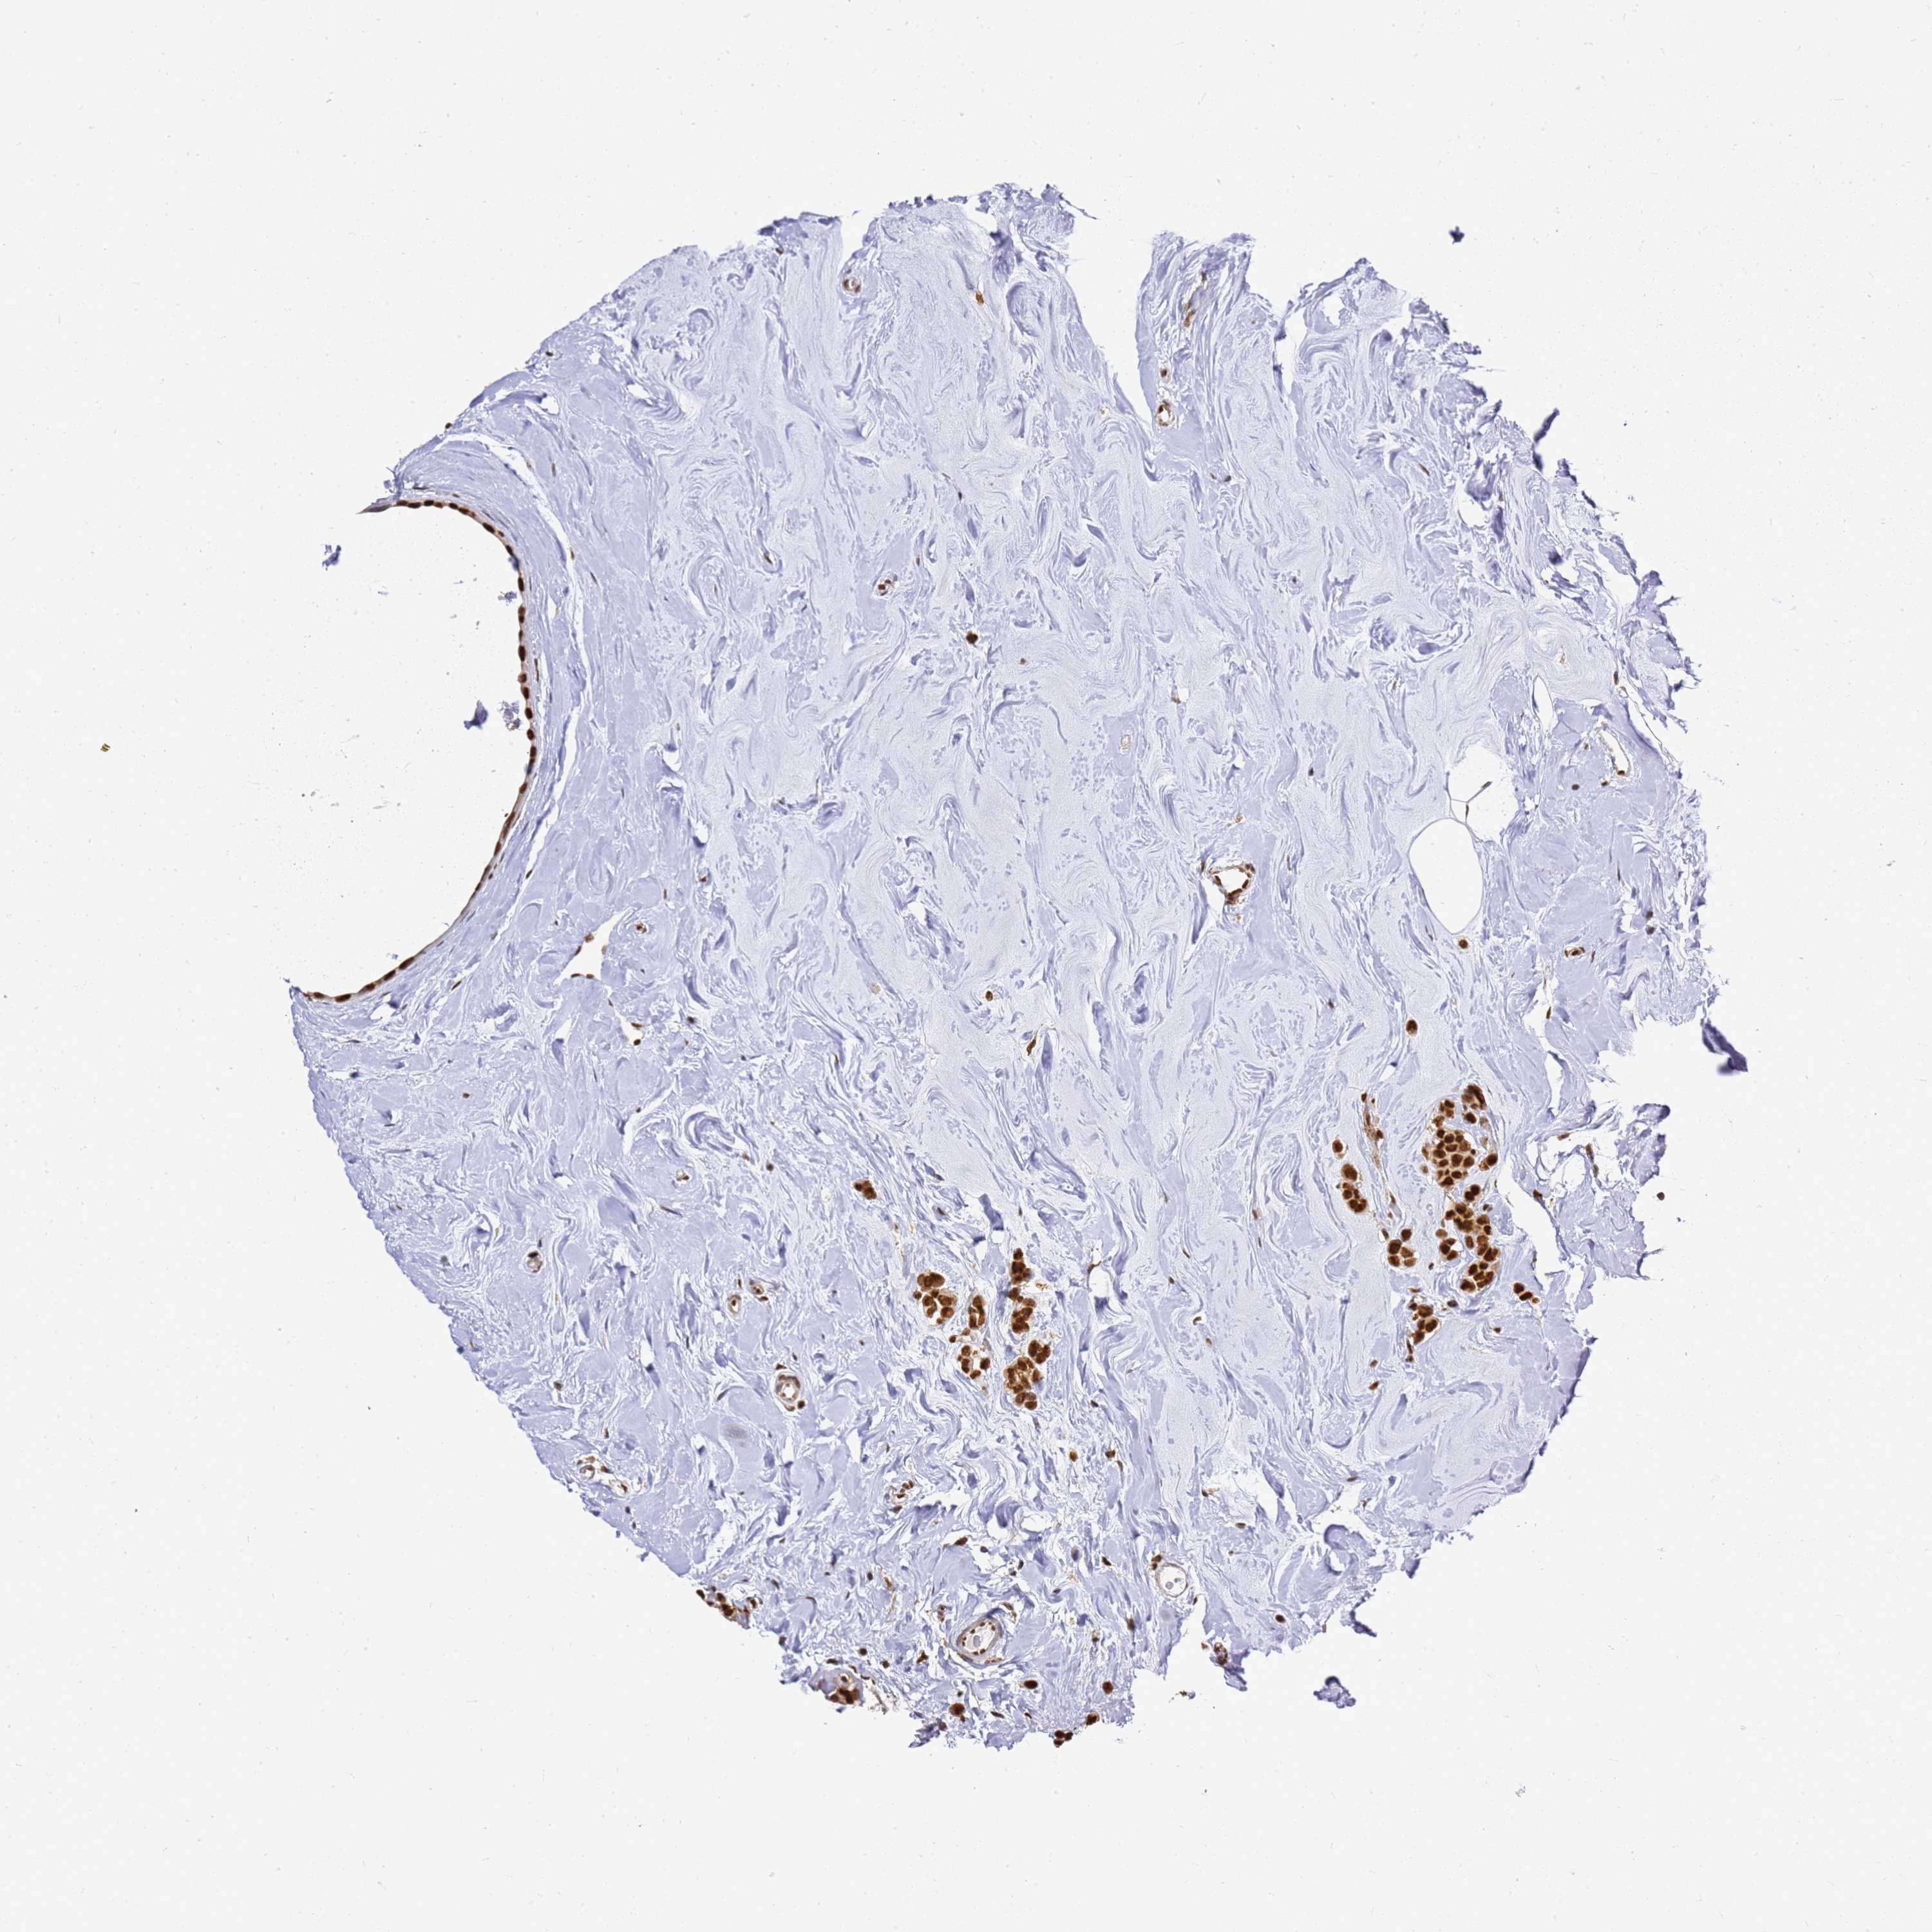

APEX1

CANCER BREAST CANCER Show tissue menu

BRCA TCGA BRCA VALIDATION PROTEIN EXPRESSION

ANTIBODIES

AND

VALIDATION